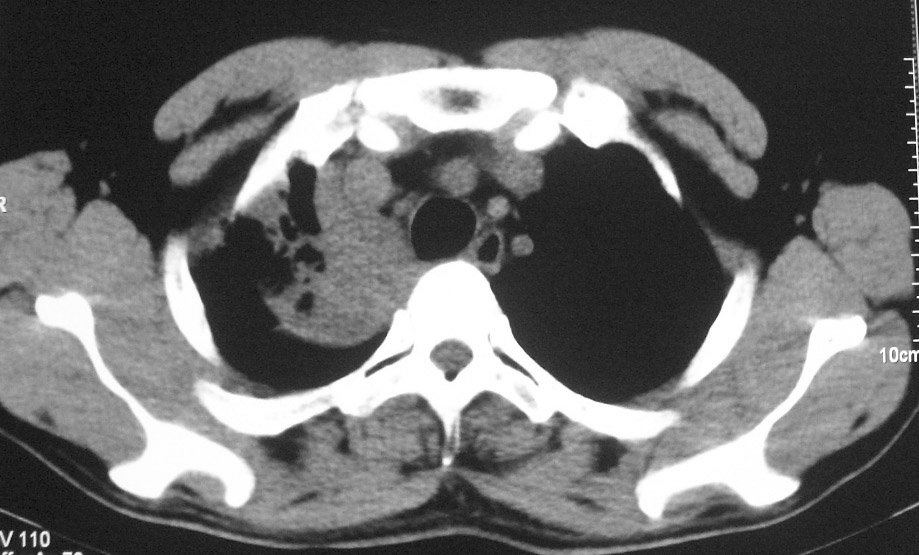

标题: CT5485:[原创]肺部占位请讨论

右肺上叶中央型肺癌并上叶肺不张、纵隔淋巴结肿大

右上叶支气管后壁明显增厚,支持右肺上叶中央型肺癌伴右上叶肺不张、纵隔淋巴结肿大。

右上叶支气管肺癌并右上叶阻塞性不张,右侧少量胸腔积液.

右上肺中央性肺癌伴右侧胸腔少量积液!右上肺胸膜下还有一小病灶,不完全排除结核,但个人支持恶性肿瘤!建议早穿刺活检。

右肺上叶中央型肺癌并上叶肺不张、纵隔淋巴结肿大.右侧少量胸腔积液。